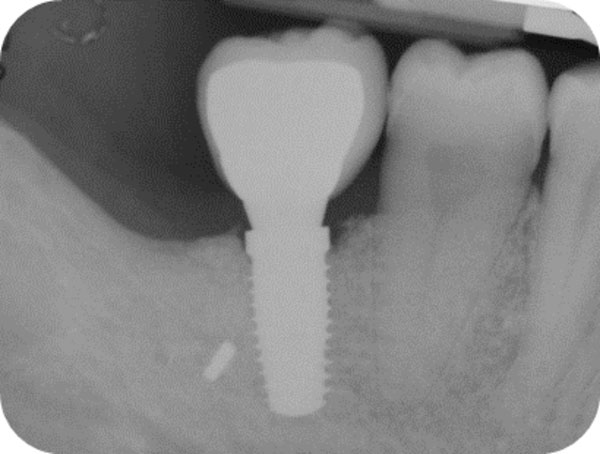

Follow-up x-ray at 1-month.

Follow-up x-ray at 12-months.

After 15 days, the soft-tissue healing was uneventful, and the previously established prosthetic protocol was followed. A single-crown definitive restoration was delivered 1 month (Fig. 11a, 11b). The prosthesis was placed in occlusion, where the occlusal surface was thoroughly modeled, so that it was in contact with reduced areas during laterality and protrusion excursions, in order to reduce the dislocating vectorial components; more contacts were maintained in maximum intercuspation. Follow-up radiographs were taken at 1, 12, and 24 months after prosthesis delivery (Fig. 12, 13, 14).

One year after surgery, clinical examination showed no significant changes in the soft-tissue contours. All follow-up radiographs taken up to 24 months after implant placement showed complete maintenance of the peri-implant bone levels without any sign of bone resorption. The grafted site was perfectly able to support the functional loading of the implant.

The histologic results appear to correlate with the good clinical outcome documented by the intraoral x-rays. Indeed all follow-up controls showed complete maintenance of the peri-implant bone levels without any sign of bone resorption. The healed bone was perfectly stable up to 24 months after bone augmentation, supporting the functional loading of the implant. A possible explanation of the maintenance of bone levels and stability over time is the nearly complete resorption and substitution of the heterologous biomaterial by newly formed functional bone tissue together with the restoration of the masticatory load. The fact that control x-rays maintained the same appearance over time, showing the first implant threads in strict contact with a bone-like area, as far as both structure and radio-opacity are concerned, also suggests that the heterologous bone material may have undergone a remodeling process leading to the osseointegration of the fixture also in the biomaterial-only grafted region.